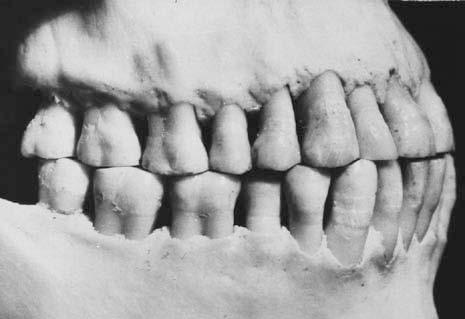

Figure 1.4 Well-interdigitated class I dentition showing diet-related occlusal interproximal wear.

dietary changes in modern societies, with increased consumption of soft, energy-rich food, has resulted in less interproximal wear between the teeth. Research on aboriginal and stone aged populations has demonstrated this lack of attrition as a possible cause of malocclusion, particularly crowding (Begg, 1954). However, it has been shown that the amount of tooth material lost in each quadrant by interproximal wear is not more than 2 to 3-mm (Fig. 1.4).